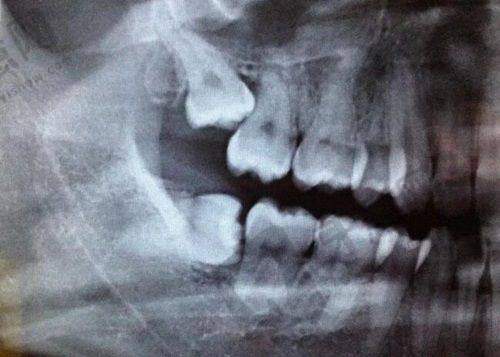

刘鹏医生是北京优贝口腔的核心人物。他拥有超10年口腔临床经验,曾在多家有医生院任职,积累了丰富实践经验。刘医生毕业于国内有医生学校,专精知识扎实、技术不错。他擅长种植牙、牙齿矫正、美学修复等多种口腔项目。在种植牙领域,能根据患者口腔状况和需求精细制定种植方案,确保种植成效稳定美观;在牙齿矫正方面,熟练掌握各种矫正技术,为患者提供个性化矫正方案,助力患者拥有整齐美观的牙齿。

在种植牙项目中,刘鹏医生凭借丰富经验和不错技术,能应对各种复杂种植情况。术前对患者全方面口腔检查评估,制定个性化种植方案;术中操作精细,确保种植体稳定性和成功几率;术后为患者提供详细护理指导,助其快速修复。众多患者在刘医生治疗下,解决牙齿缺失问题,修复正常咀嚼功能和美观。

在牙齿矫正方面,刘鹏医生擅长不拨牙隐形矫正等技术。根据患者牙齿情况和面部特征设计适合的矫正方案,矫正中密切关注牙齿移动情况,及时调整矫正力度,确保矫正成效至佳。其矫正方案不仅让牙齿整齐美观,还能改善面部轮廓,提升患者整体形象。